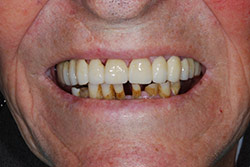

Con protesi fissa superiore e protesi fissa inferiore

I denti irrecuperabili dell'arcata superiore ed inferiore del paziente di anni 65

sono stati sostituiti da 10 impianti, cioè protesi radicolari endo-ossee che sostengono le protesi fisse superiore ed inferiore.